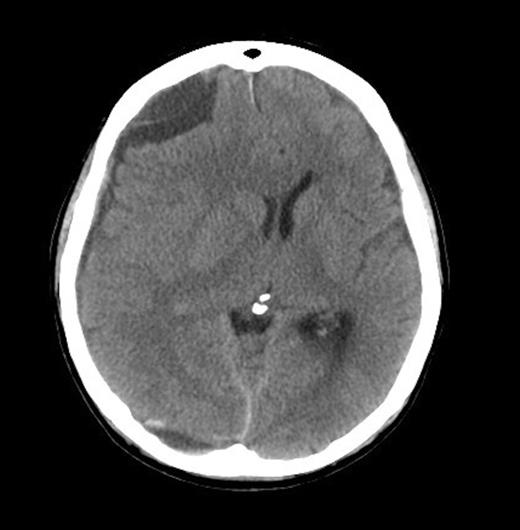

A 62-year old male presented to the emergency department of our institution with epistaxis, anaemia (Hb: 48g/L) and thrombocytopenia (platelets: 52x109/L). Past history included a diagnosis of metastatic prostate adenocarcinoma 7 years earlier. He denied headaches and there were no neurological deficits other than mild cognitive impairment. He was noted to be coagulopathic with an INR of 1.5, despite platelet, fresh frozen plasma and red blood cell transfusion, his coagulopathy ultimately worsened. His level of consciousness deteriorated and a CT Brain was performed identifying acute on chronic SDH (Figure 1 & 2).

He received further platelet and plasma transfusion to correct his INR of 3.5, and was taken to theatre where a right parietal craniotomy and left parietal burrhole were performed to evacuate the SDH. Intraoperatively, the dura was noted to be thickened and subdural membrane tissue was obtained for histopathology. This was consistent with metastatic adenocarcinoma of the prostate (Figure 3 & 4). The patient recovered well day one post-operatively with no neurological deficits. His level of consciousness rapidly deteriorated on day two post-operatively, with no evidence of haematoma recurrence or neurosurgical complication on repeat CT Brain. The patient subsequently died on post-operative day four.